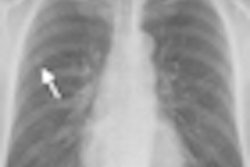

Patients with spinal deformities such as scoliosis often require multiple radiographs for follow-up throughout childhood and adolescence, a practice pattern that has caused concern due to radiation exposure, the authors noted. The EOS system uses a slot-scanning design that results in lower radiation dose, while producing 2D and 3D images that have more clinical potential that conventional DR, according to the authors.

Images for the EOS system in terms of global image quality were rated as better than CR for 46.7% of cases, equivalent to CR in 50.5%, and worse than CR in 2.8%. In terms of structure visibility, EOS was rated as better than CR in 32.4% of cases, equivalent to CR in 61.9%, and worse in 5.7%.

The authors concluded that the EOS unit has better image quality with lower dose, and the system's potential to acquire 2D orthogonal images to facilitate 3D surface reconstruction of the vertebrae and pelvis could have potential.